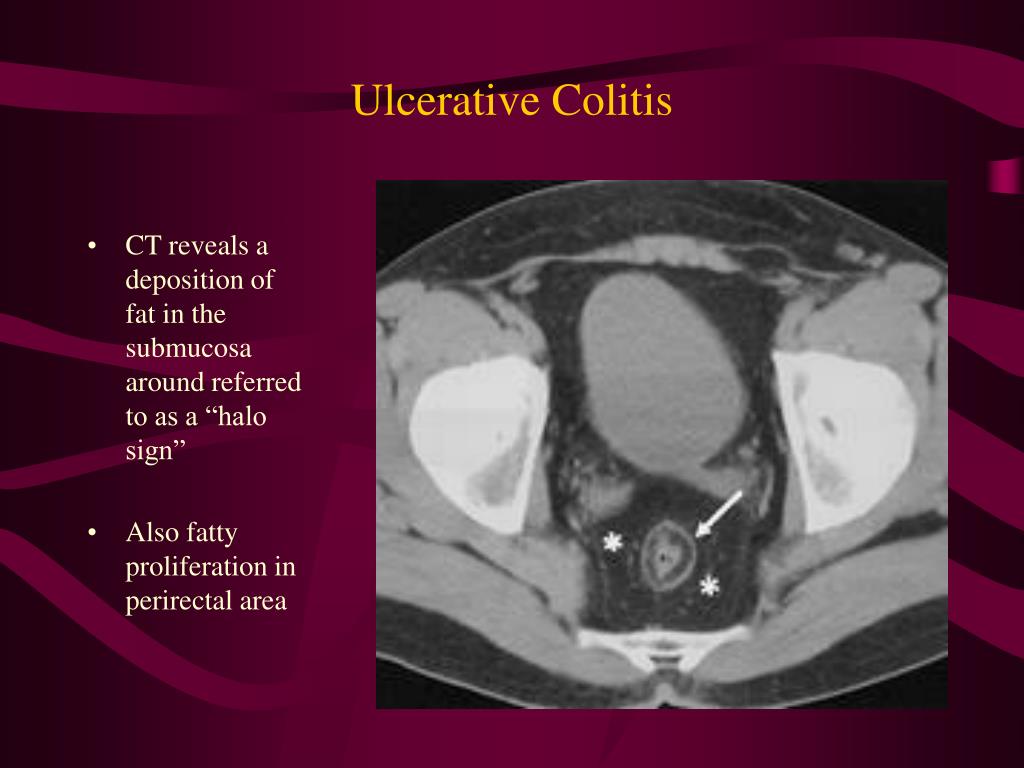

Ulcerative Colitis

From www.slideserve.com

PPT Radiographic findings in Ulcerative Colitis and Crohn Disease Burning Eyes Ulcerative Colitis It is a systemic disease that affects other organs,. In most people, symptoms usually. Ulcerative colitis (uc) is a type of inflammatory bowel disease (ibd) that affects the large intestine and rectum. Ulcerative colitis affects the innermost lining of your large intestine, also called the colon, and rectum. It is important to remember that ibd affects not just your abdomen;. Burning Eyes Ulcerative Colitis.